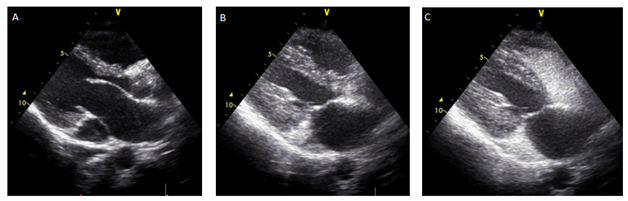

Transtorasik EXO zamanı koronar sinusun genişləndiyi görüldü. Sağ tərəf ürək boşluqları normal genişlikdə idi. Trikuspid requrgitasiya velositəsi ilə sistolik pulmonar arteriya təzyiqi 28 mmHg olaraq ölçüldü. Persistan sol superior vena kava (PSSVK) haqqında şübhə yarandı. Sol üst ekstremitə venasından agite olunmuş salin (“babl” testi) bolus şəklində inyeksiya edildi, əvvəlcə koronar sinus doldu, ardınca ürəyin sağ boşluqlarında qabarcıqlar görüldü (Şəkil 2). Ürəyin sol boşluqlarında qabarcıq müşahidə edilmədi.

Şəkil 2. Sol qol venasından inyeksiya edilən “agite salin”dən əvvəl və sonra əldə edilən ardıcıl görüntülər koronar sinus vasitəsiylə sağ atriyuma açılan persistan sol superior vena kava diaqnozunu təsdiqləmişdir. A) kontrastsız görüntü, dilate koronar sinus (ölçüləri 22x27 mm). B) “babl”lar sağ ventrikuldan əvvəl koronar sinusu doldurmuşdur. C) sağ boşluqlar opaklaşmışdır. Sol boşluqlara keçiş yoxdur.